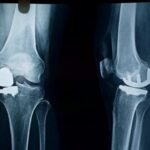

Partial Knee Replacement Surgery

Partial knee replacement is a surgical procedure in which only the damaged portion of the knee joint is replaced, while the healthy parts of the knee are preserved. Unlike total knee replacement, this surgery focuses on the specific area of the knee affected by arthritis, most commonly the inner (medial) compartment.

Because much of the natural knee structure is maintained, partial knee replacement aims to relieve pain while allowing more natural knee movement.

Partial knee replacement is suitable for selected patients with arthritis limited to one part of the knee. It is not a replacement for total knee surgery in all cases. The choice depends on individual knee condition.